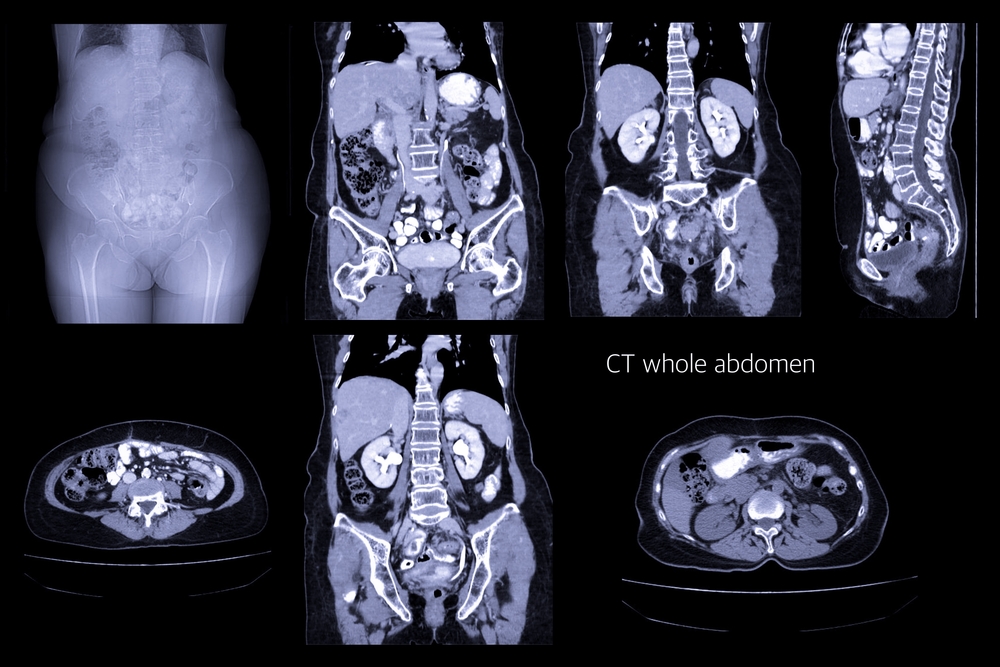

FAP Imaging study

Body-wide imaging can detect amyloid protein deposits in the organs of people with familial amyloid polyneuropathy (FAP), making it possible to assess the effects of new therapies without performing invasive tissue biopsies, a Japanese study reports.

Researchers at Japan’s Shinshu University School of Medicine used an imaging technique called positron emission tomography. PET scans work by emitting a radioactive tracer molecule that binds to a target molecule.

They discovered that the imaging detected high levels of amyloid in the heart and stomach, which correlated with FAP and AL’s manifestations.

In addition, imaging did not detect amyloid deposits in the peripheral nervous system — the parts of the system outside the brain and spinal cord. This was despite the fact that six FAP patients and one AL patient were experiencing obvious nerve malfunctioning.

As an additional test, researchers compared the scan results with the amount of amyloid in tissue samples. They concluded that imaging identified amyloid deposits as examining tissue with a microscope.